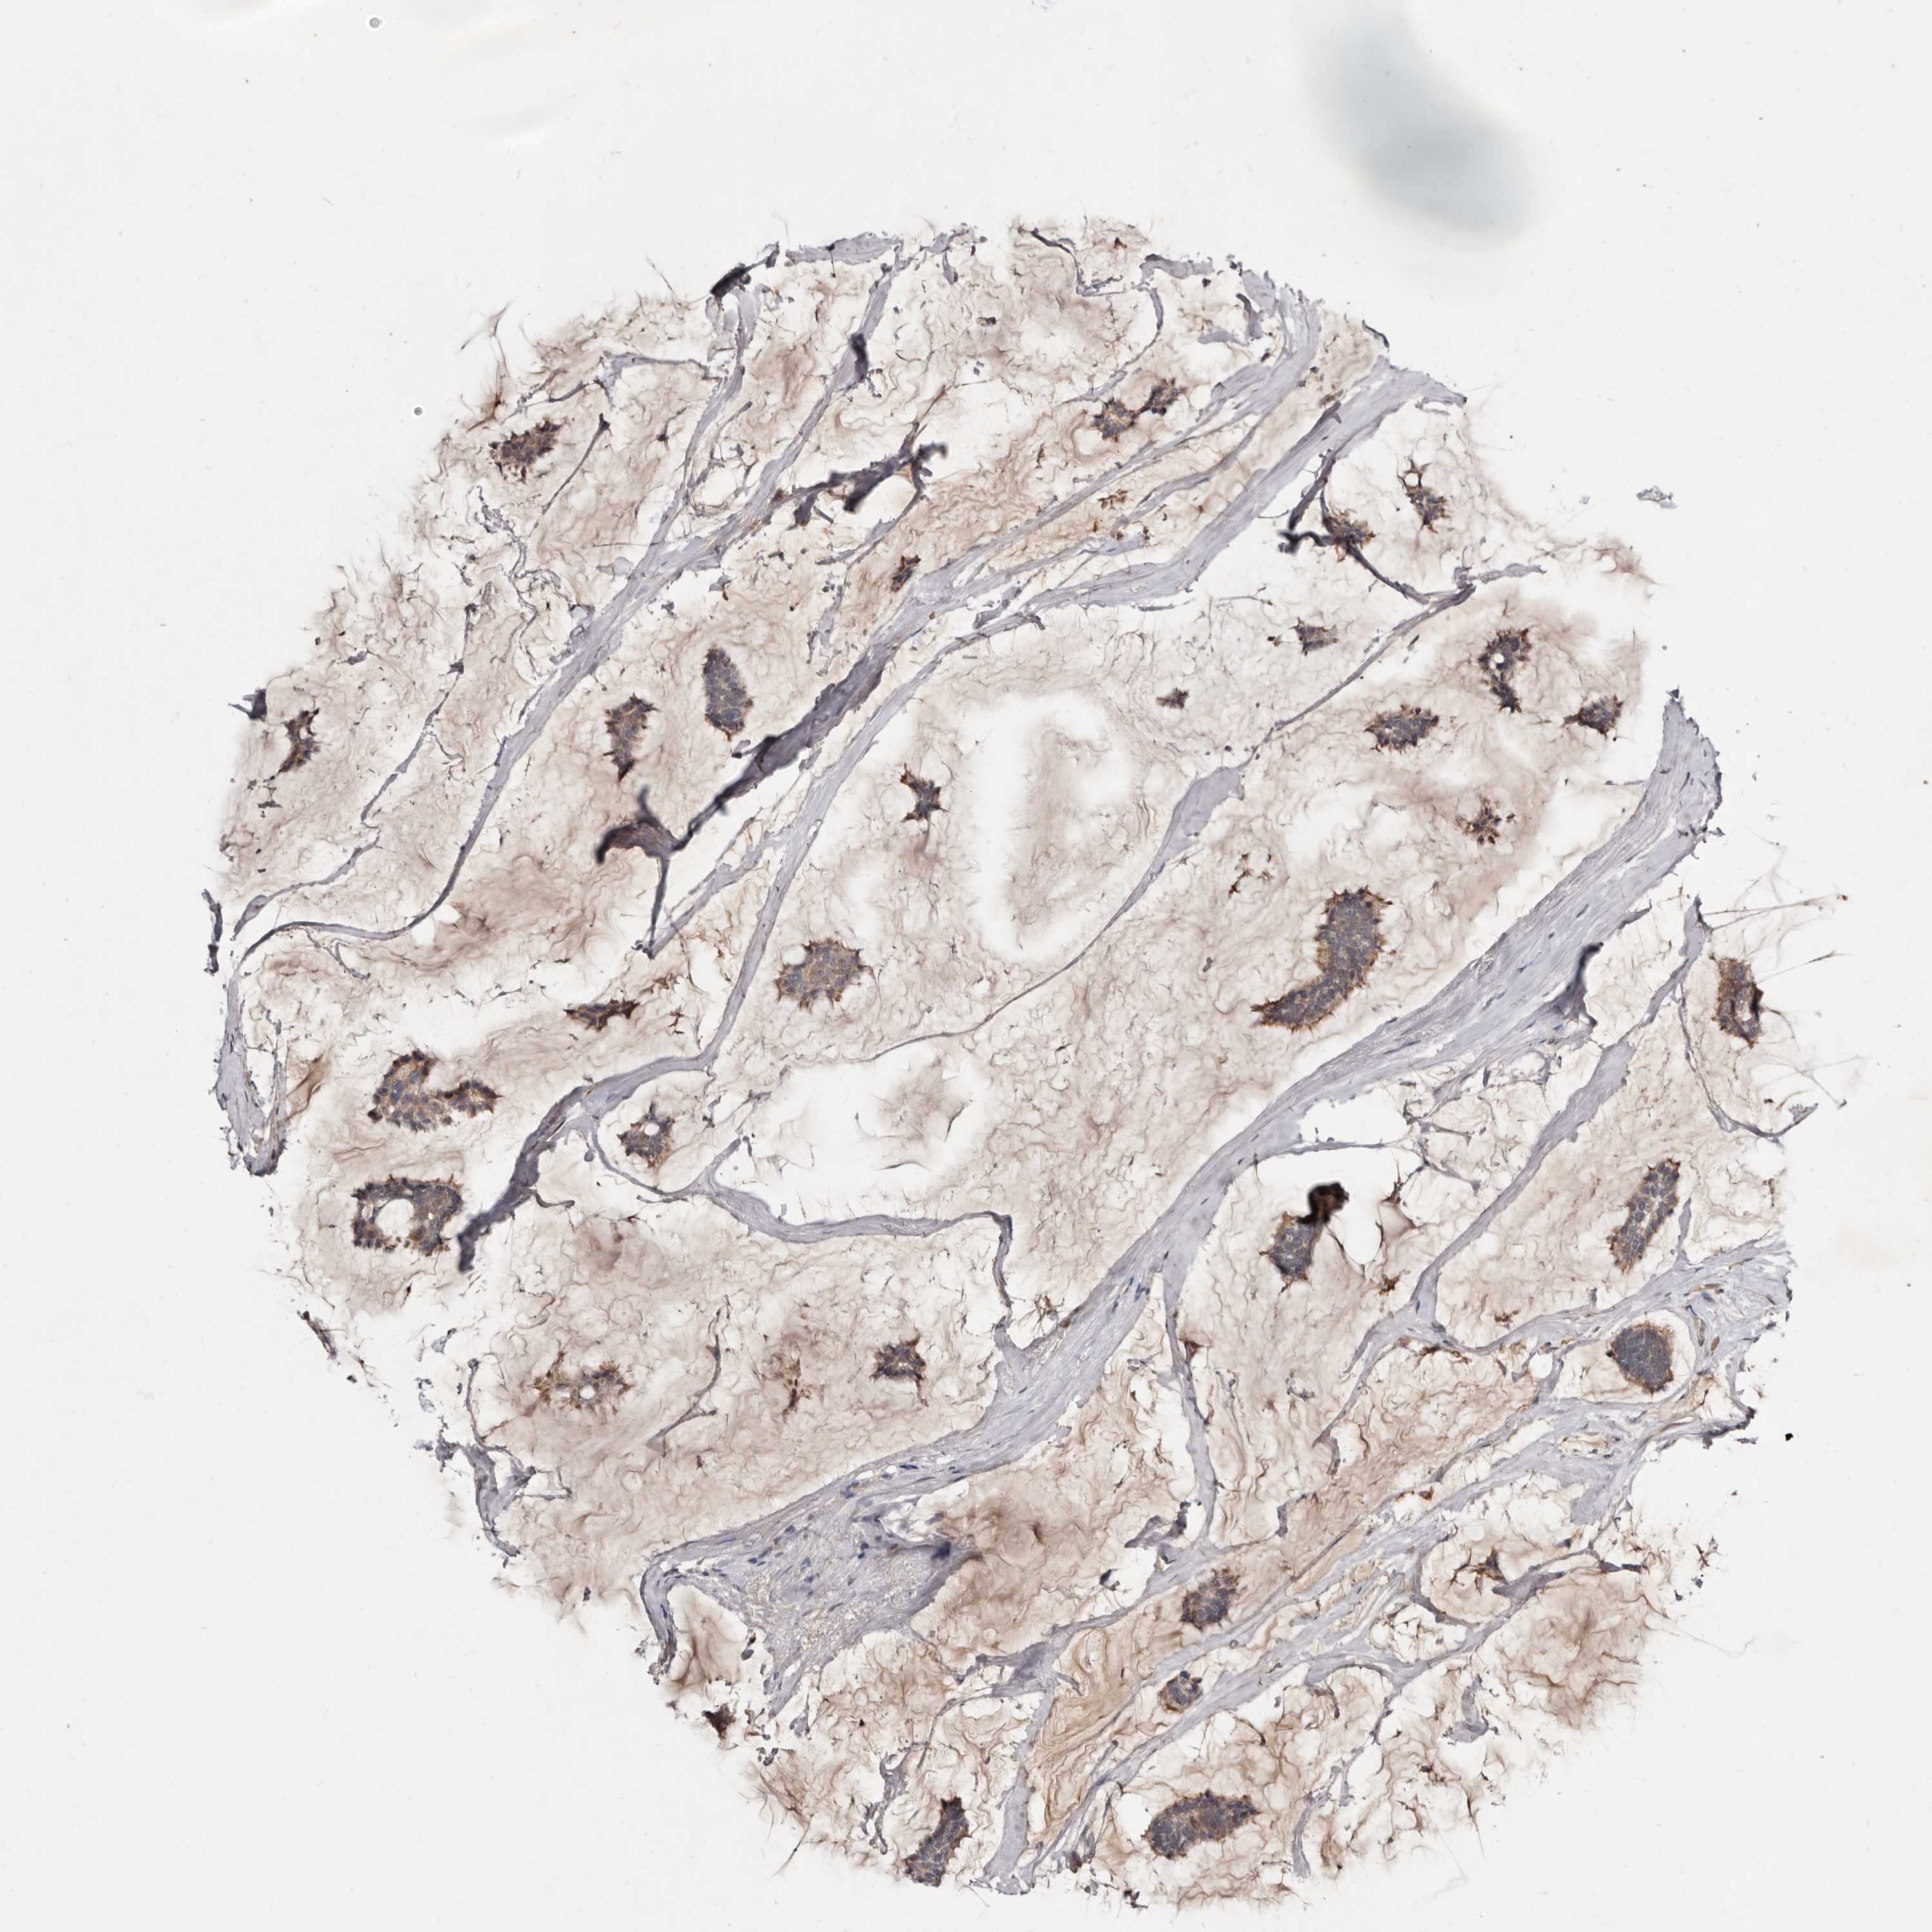

CANCER BREAST CANCER Show tissue menu

BRCA TCGA BRCA VALIDATION PROTEIN EXPRESSION